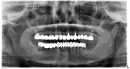

Оценив панорамный рентгеновский снимок ваших зубов, можно сказать, что оставить на нижней челюсти можно только 2 зуба - это клыки. Остальные удалять, шестые зубы из-за чрезмерной нагрузки мостовидного протеза на них находятся практически не в костной ткани, их корни резорбированы. У верхушки корня пятого и четвертого зуба есть воспалительный процесс.

Желательно перед имплантацией провести лечение десен, но если у хирурга есть опыт работы с пациентами, у которых есть заболевания пародонта, то не нужно. Можно провести операцию по имплантации зубов более дорогой, безболезненный, но эстетичный , гипоаллергенный, комфортный, долговечный способ замещения отсутствующих зубов. Или частичный съёмный протез - дешевый вид протезирования, но доставляет дискомфорт пациенту так как достаточно громоздкий и не многие могут к нему привыкнуть.